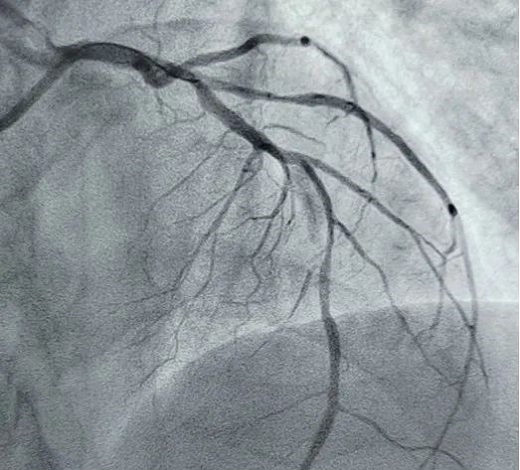

立即啟動綠色通道,急診冠脈造影,結(jié)果顯示前降支近段閉塞,血栓負(fù)荷較重,先后給予血栓抽吸及球囊擴張,血流恢復(fù)正常。李桂武主任和劉興剛主任發(fā)現(xiàn)患者近段狹窄達70%,且中遠(yuǎn)段嚴(yán)重狹窄伴鈣化,此時不適合同期植入支架,如植入支架可能會引發(fā)血管破裂危及生命。當(dāng)務(wù)之急是快速評估出患者是否可以下手術(shù)臺,選擇擇期進行處理,但僅根據(jù)造影結(jié)果又很難做出判斷,李桂武主任和劉興剛主任快速討論研究最后一致決定,給予患者行冠脈OCT檢查,明確病變性質(zhì)。

經(jīng)OCT檢查結(jié)果顯示:前降支中段鈣化,內(nèi)膜光滑,最小管腔面積僅為1.19 mm2。近段斑塊破裂,可見血栓影,最小面積為2.63mm2??蛇x擇先進行抗栓治療,擇期處理冠脈病變。這讓張先生懸著的一顆心終于放下來。